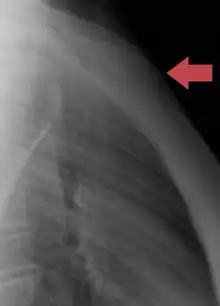

Fractures

Fractures of the sternum are rather uncommon. They may result from trauma, such as when a driver's chest is forced into the steering column of a car in a car accident. A fracture of the sternum is usually a comminuted fracture. The most common site of sternal fractures is at the sternal angle. Some studies reveal that repeated punches or continual beatings, sometimes called "breastbone punches", to the sternum area have also caused fractured sternums. Those are known to have occurred in contact sports such as hockey and football. Sternal fractures are frequently associated with underlying injuries such as pulmonary contusions, or bruised lung tissue.[13]